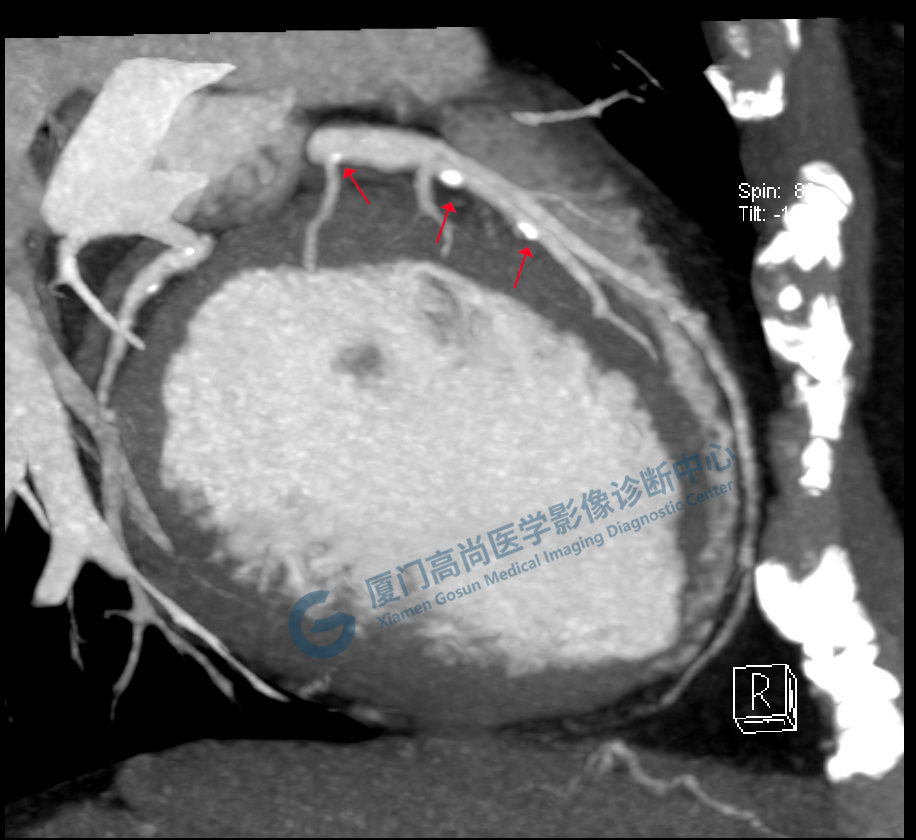

冠脈CTA圖像

左、右冠開(kāi)口

冠狀CTA右冠

回旋支

前降支

圖像所見(jiàn):左冠狀動(dòng)脈前降支,前降支近段可見(jiàn)局部鈣化斑塊,管腔狹窄約5%,左側(cè)冠狀動(dòng)脈對(duì)角支可見(jiàn)鈣化斑塊,管腔狹窄約20%-30%。

左冠狀動(dòng)脈回旋支,近段可見(jiàn)局部鈣化斑塊,管腔狹窄約5%-10%。

影像診斷:CAD-RADS分級(jí):2(25%-49%),輕度狹窄。